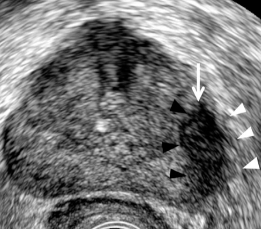

Identify this image.

Prostatic cancer